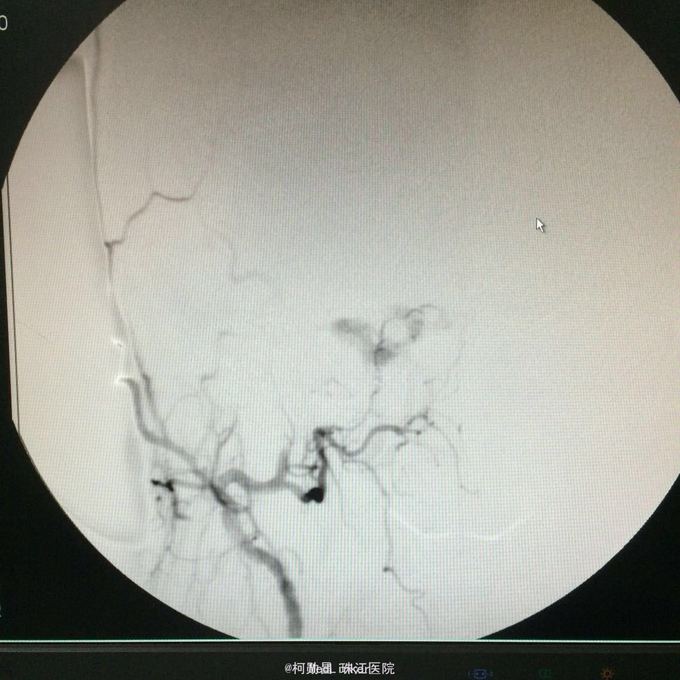

查体:右眼结膜充血水肿,活动不受限,余神经系统查体未见明显异常。 辅助检查:行头颅DSA提示右侧海绵窦硬脑膜动静脉瘘

诊断:右侧海绵窦区硬脑膜动静脉瘘 处理:行血管内介入治疗,经右侧脑膜中动脉注入onyx胶栓塞